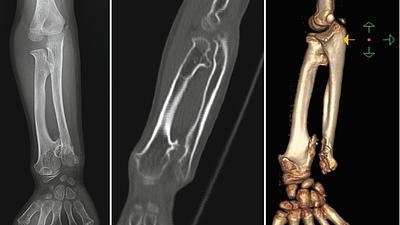

SUS amplia capacidade de diagnóstico para o Distrito Federal

O Tomógrafo Computadorizado Multislice é um equipamento capaz de realizar 1,2 mil exames ao mês podendo atingir cerca de 15 mil tomografias ao ano.